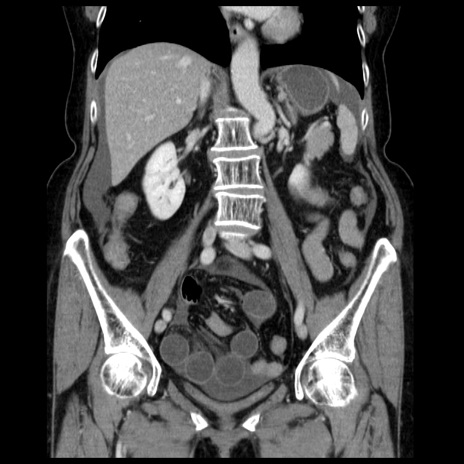

症例13(冠状断像)

【症例】70歳代女性

【主訴】腹痛、嘔吐

【現病歴】15時間程前(昨晩)より腹痛あり。今朝になっても症状の改善なく、嘔吐あり。腹痛も増悪あり、救急外来受診。

【既往歴】子宮癌全摘術後

【身体所見】意識清明、BP 121/72mmHg、P 74bpm、SpO2 100%(RA)、腹部:平坦・軟、腸雑音ほぼ聴取せず。下腹部・心窩部・臍左上に圧痛あり。反跳痛なし。

【データ】WBC 10600、CRP 0.15